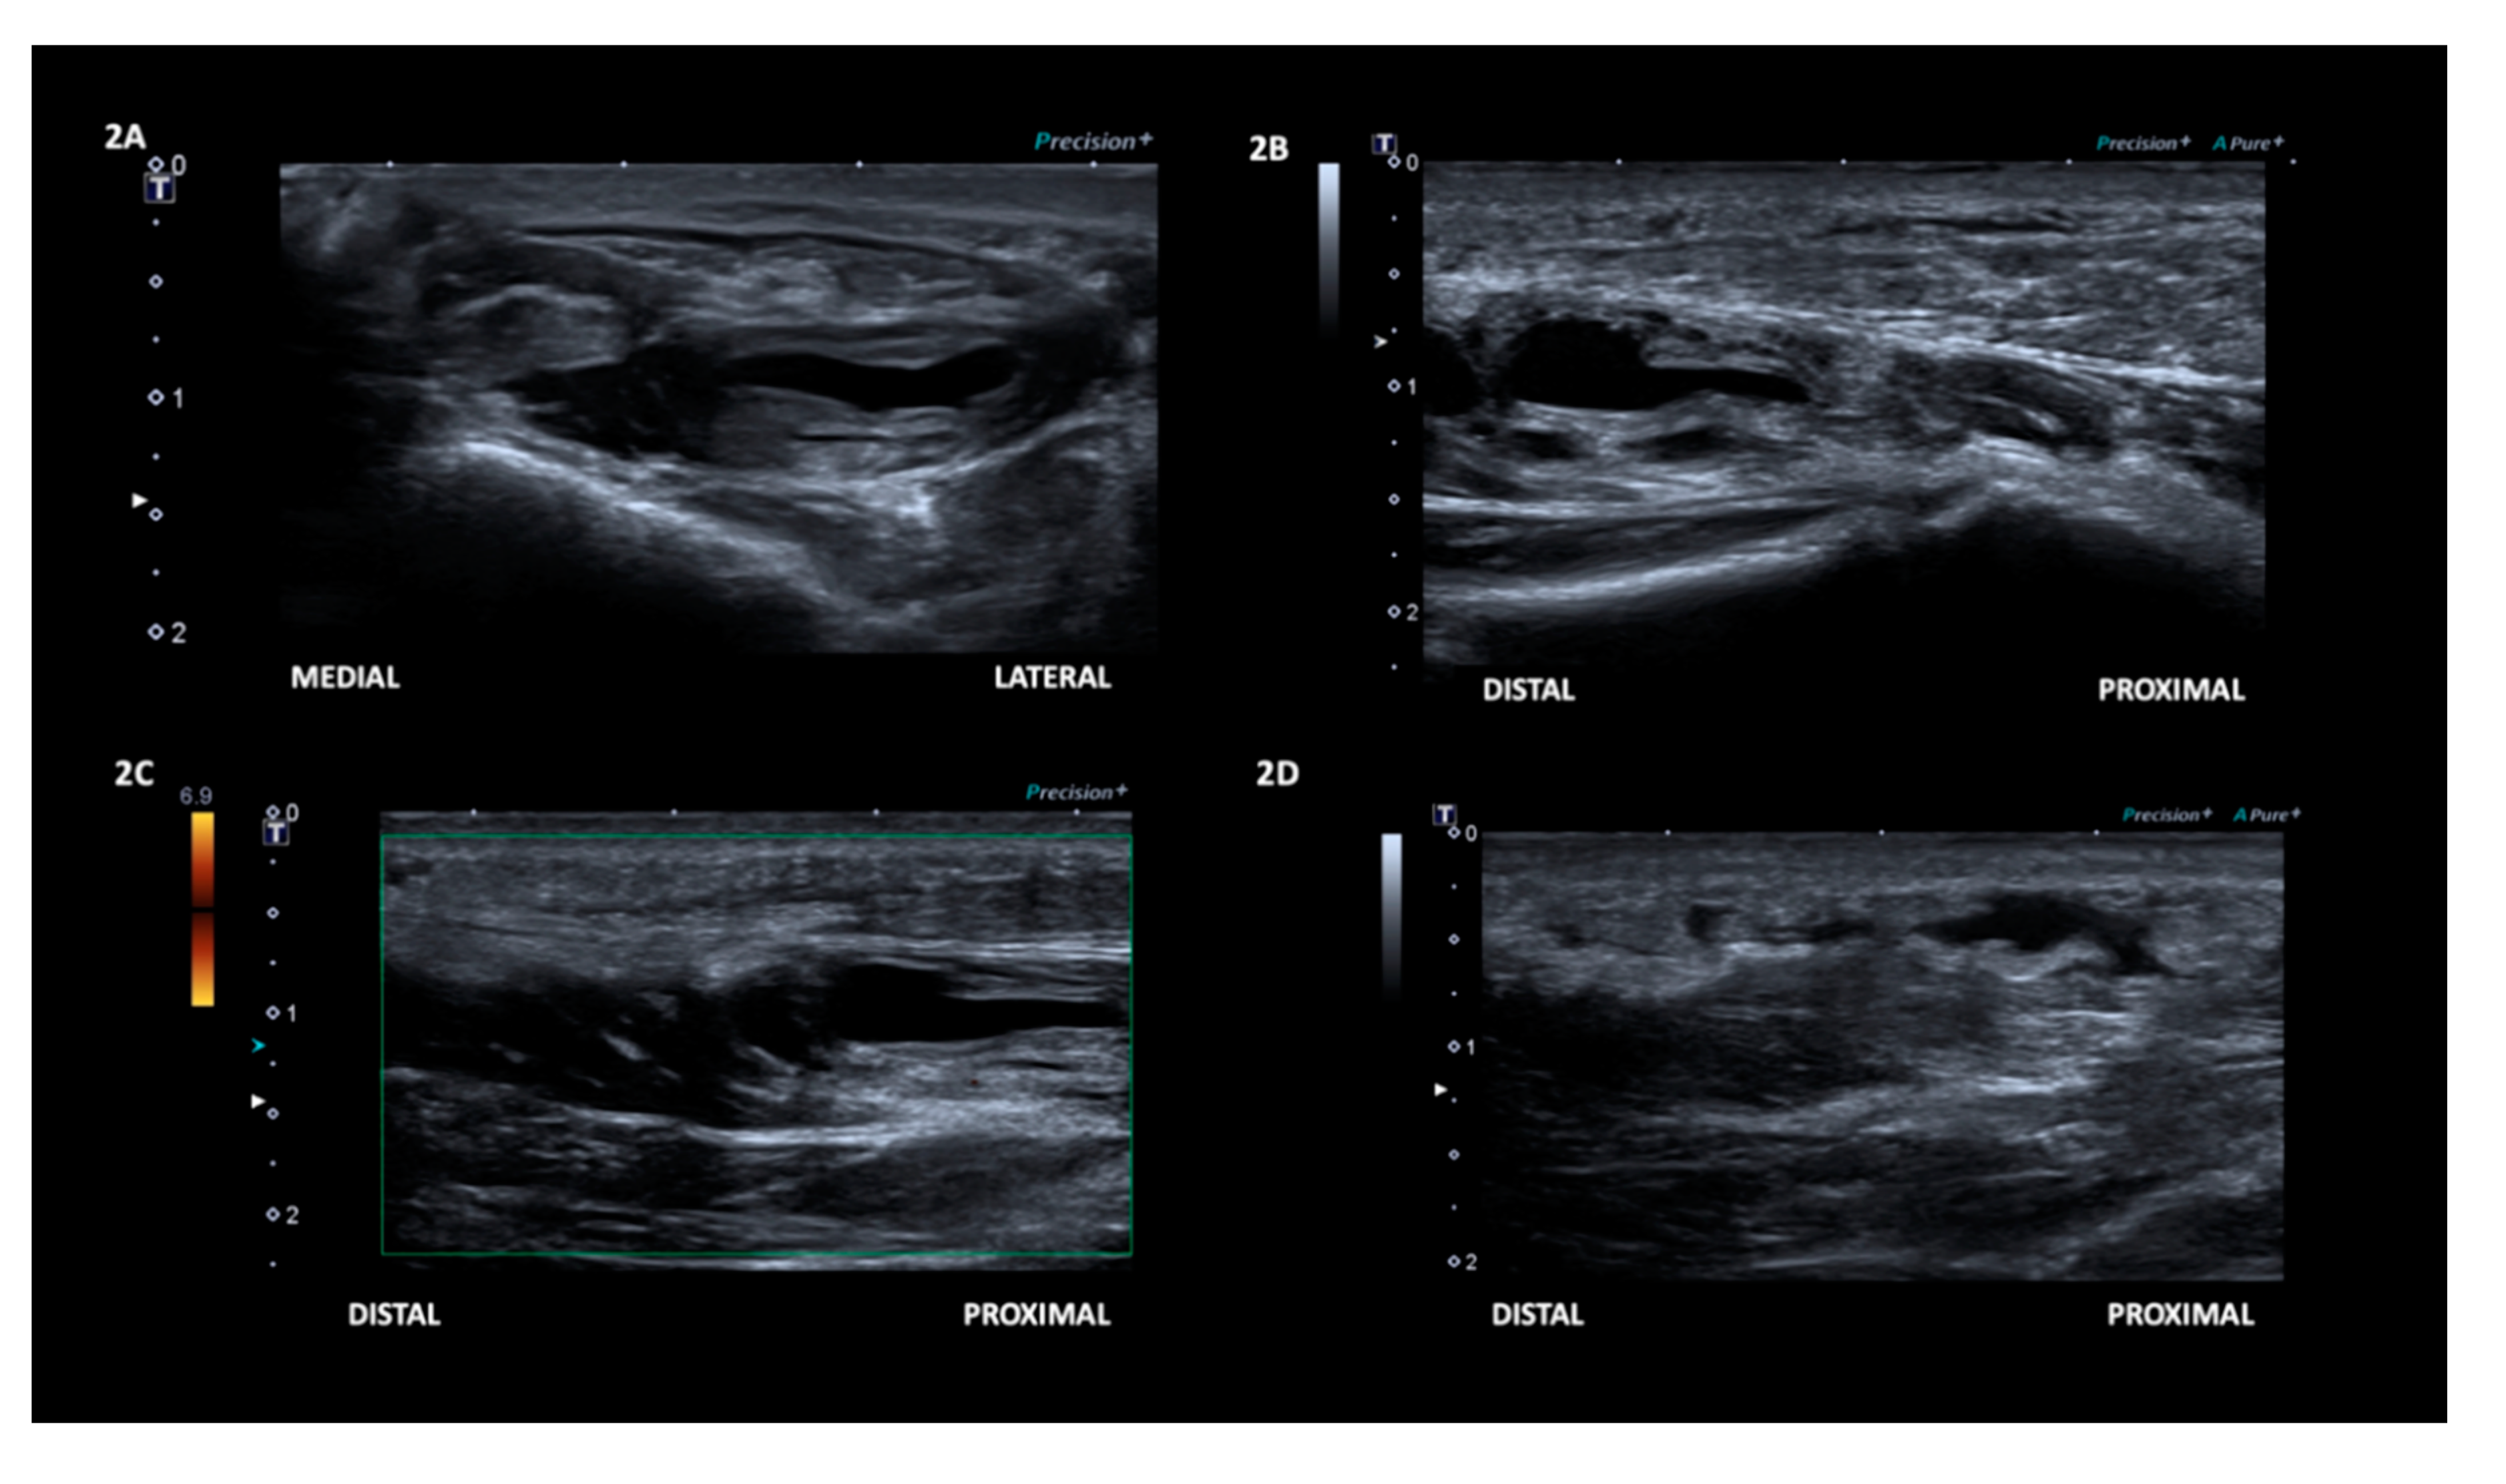

2. Case Presentation